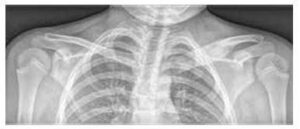

Obrázok č. 1

Palmoplantárna pustulóza u pacienta s CRMO

Najčastejšie postihnutými kosťami sú metafýzy dlhých kostí, kľúčna kosť, telá stavcov a panva (pozri obrázok 2). Počet kostných lézií sa líši (niekedy ide len o jednu léziu, častejšie o viacero lézií). Niekedy sa aj asymptomatické lézie odhalia pomocou kostnej scintigrafie alebo magnetickej rezonancie celého tela (WB MRI).